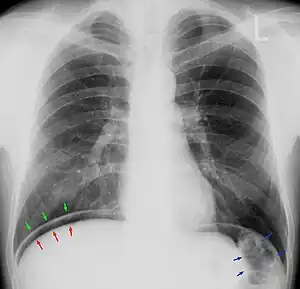

| Chest X-ray with air between the right diaphragm and the liver (green and red arrows). Air also visible below the diaphragm on the persons left. Blue arrows mark a normal gas filled colon. | |